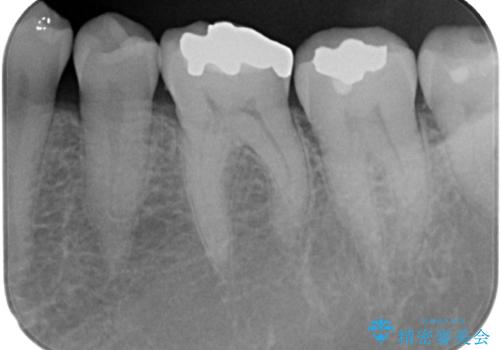

- 銀歯の周りに物が挟まるとのことで来院された患者様です。

咬合力が強く、銀歯周りの歯質に隙間が生じてむし歯になっている状態でした。

むし歯をしっかりと取り除き、強い咬合力を考慮してゴールドインレーにて修復することとしました。

ゴールドインレーは銀歯のインレーやセラミックインレーと比べ、「技工操作の精度が高く、適合が著しく良い」というメリットがあります。特に「適合の良さ」は再治療のリスクを防ぐ上でとても重要な要素となります。

咬み心地はとても良好で、全く違和感がなく、患者様には大変満足していただきました。